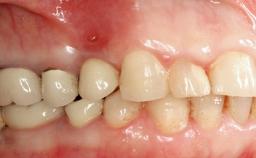

Peripheral Giant-cell Granuloma Associated with Peri-implant Tissues

Prosthesis Type FDP

SAC Level Advanced

Defining Characteristics Up to three missing teeth to be replaced with an implant-borne restoration or restorations